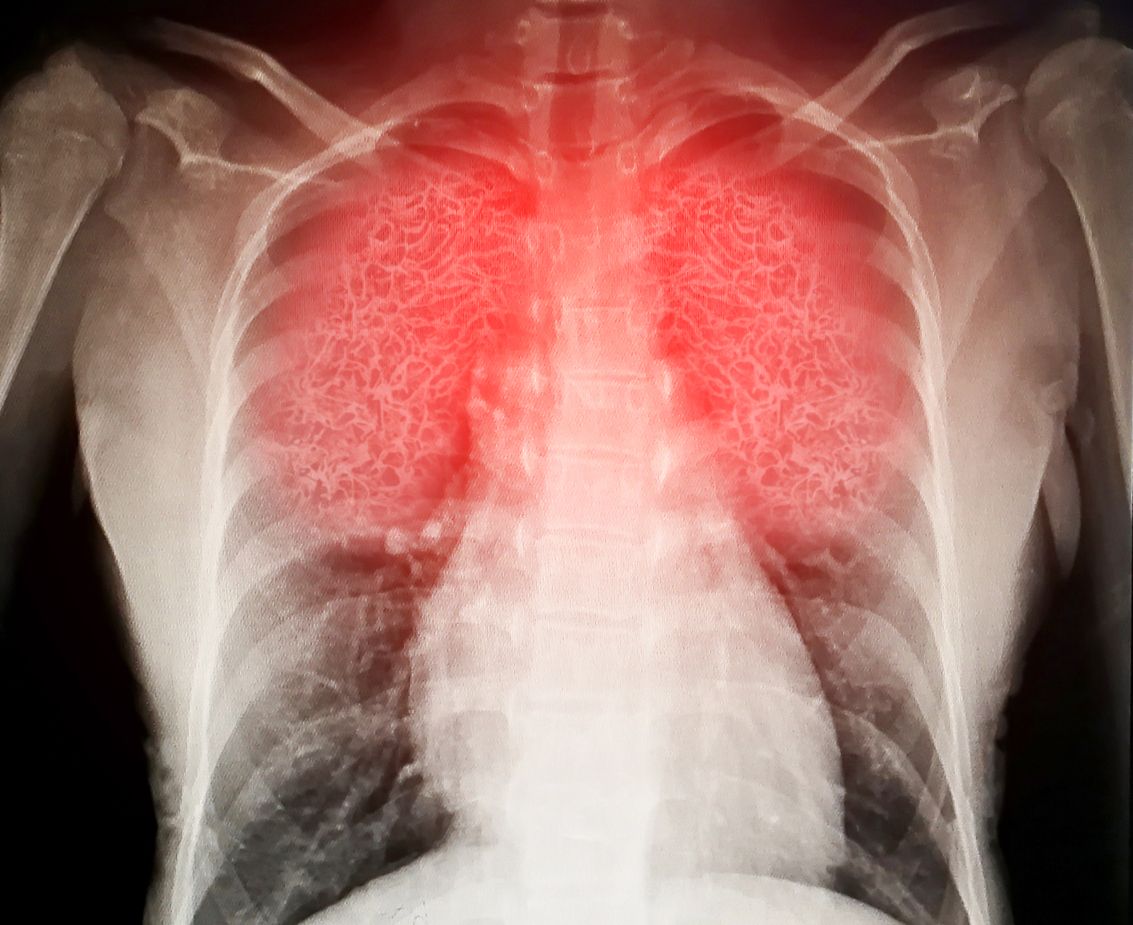

Der Blick durch das Mikroskop zeigt das Ausmaß der Covid-Lungenschäden: Zerstörte Lungenbläschen, die Wände deutlich verdickt und eine ausgeprägte Bildung von Narbengewebe.

Virus destroys human lungs the lnflamed a radiograph